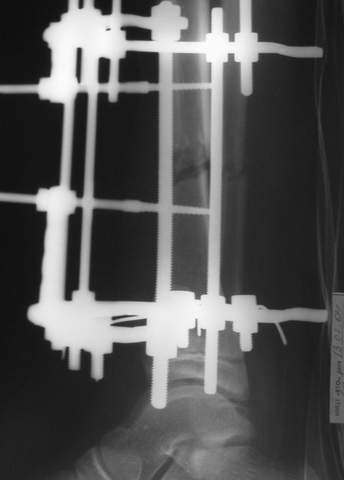

3a

3b

3c

В аттачте № 3 - один из примеров полукольцевого аппарат...

Это уже я баловался.

Итог? Работы больше (по времени и

интраоп "подгонке"), срастается также, а особого преимущества по сравнению с

"чиста" кольцевым (вес, удобство ношения и пр.) - я, по крайней мере,

не нашел.

Теперь не балуюсь.

Может быть зря?